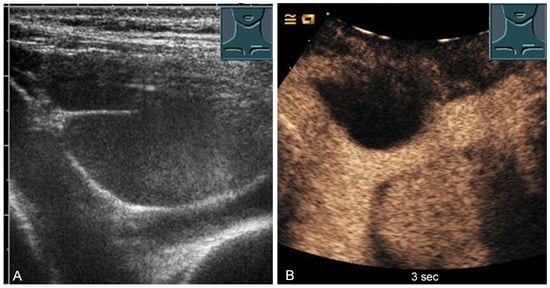

The thickness increase during inspiration was also used as a measure of muscle contraction. In most studies, an increase during inspiration of >20% is considered as normal [55] (Figure 31).

Figure 31.

Representation of diaphragm thickness in expiration (A) and inspiration (B) in pleural effusion (PE) and ascites (As).